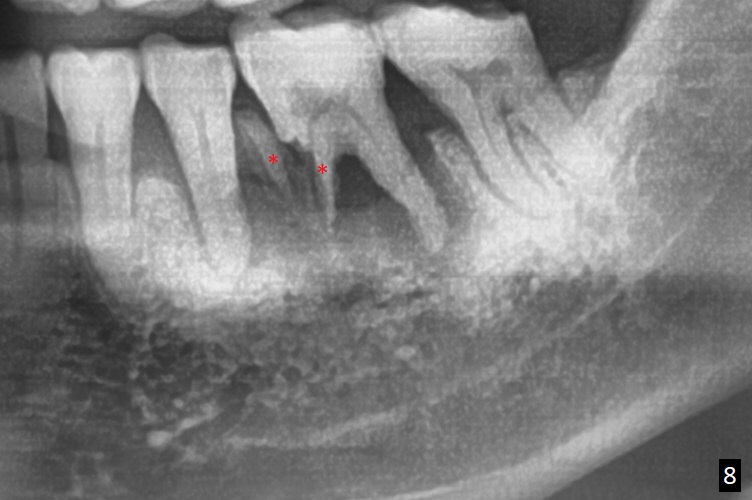

A 63-year-old man is a diabetic with history of good control. He masticates unilaterally with missing teeth #2,3 and 24 (Fig.1 (taken 5 years ago)). The latter has been restored with an implant. Last February the mesial root of the tooth #19 was found to have vertical fracture with bone loss until the base of the septum (Fig.2). The bone available for implantation is ~7-8 mm after root fracture (Fig.3,4). The initial osteotomy depth will be 7 mm (IS kit), followed by the calibrated parallel pin. The latter determines how many millimeters of an implant will be surrounded by the graft bone (Fig.4,5 (green: implant length; pink: cuff; blue: abutment length)). Since the buccal defect is severe with mesial root split (Fig.7 *), draw blood for PRF (2 large tubes). To save the remaining septum, place 2 of 1-piece implants on the either side of the septum (compare Fig.6,8). Take photos to compare buccal vs. lingual gingival recession. Tell the patient that the tooth #20 may be nonsalvageable. Since insurance preauthorization does not get approval for several times, the tooth #19 is extracted with socket preservation and periodontal dressing. The latter dislodges in 1 day. When the patient returns for follow up 4 days postop, the socket is exposed (Fig.9). An immediate implant should have been placed to keep the graft in place. PRF also helps. In fact preauthorization letter arrived 1 day earlier. It appears that guided surgery is indicated for limited bone height. The bone graft appears to gain ~ 5 mm bone in 4 months (Fig.10), which allows to place a 5x8.5 mm implant (Fig.11).